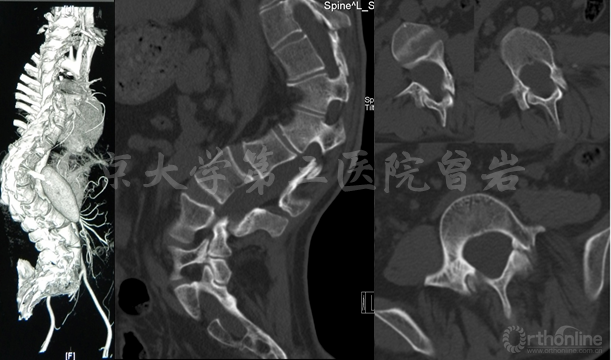

术前X线(图5):侧凸上胸弯Cobb 52°,下胸弯Cobb 52°,胸腰弯Cobb 65°,后凸角度102°,左肩高于右肩。

左右Bending X线(图6):左侧Bending上胸弯矫正至46°,胸腰弯矫正至56°;右侧Bending下胸弯矫正至48°。

CT(图7):显示脊柱侧后凸畸形,腰骶段椎管扩大,椎体扇贝样改变,椎弓根发育异常,L5峡部不连。

矫形手术设计理念:

该患者在12-13岁逐渐发现脊柱侧弯,其属于青春发育期,即第二次生长高峰时期发生脊柱畸形的MFS。大样本的研究显示,至骨骼发育成熟时,63%的MFS患者合并脊柱侧凸,其常见弯型与特发性侧凸类似,但是多发弯或大弯的比例高于特发性侧凸,且较后者僵硬的多。

另外,MFS侧弯常伴有矢状面的改变,如胸椎和胸腰段的后凸。本患者上胸弯、下胸弯和胸腰弯均为结构性弯,且较僵硬,同时伴有胸腰段重度后凸。虽然经过2周的腋下-骨盆悬吊皮牵引,但畸形未见明显减轻。

因此,手术应行三弯融合,同时矫正后凸,还应兼顾L5峡部不连。手术融合范围为T2-L5。为了获得良好的矫形,在胸腰段主弯+后凸区域行3-4级截骨,在胸段行多节段Ponte截骨。术中椎弓根置钉应注意椎弓根发育异常和细小变窄等情况。

该患者为马凡综合征性脊柱侧后凸畸形,多发弯且柔韧性差,同时伴有骨性结构发育异常,腰骶段椎管扩大,硬膜囊扩张,椎弓根发育异常,L5双侧峡部不连,手术难度较大。

术前设计为融合三弯,同时矫正后凸。针对胸腰段侧后凸顶点行不对称PSO截骨,对胸弯行多节段Ponte截骨。由于存在多发椎弓根发育异常,因此椎弓根置钉采用导航与徒手相结合,既提高准确性,又兼顾效率。矫形后应用卫星棒行L5峡部修补后的固定,以避免主固定棒与椎板钩之间的连接困难问题。